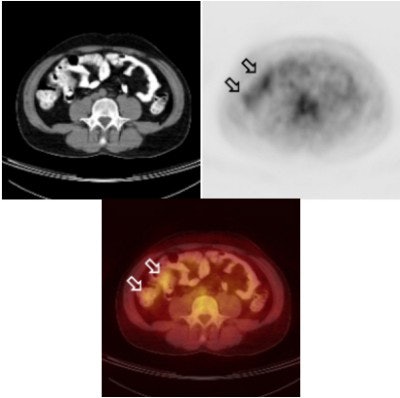

![]() |

| CT (left), PET (right), and PET/CT (bottom) with barium as an oral contrast agent demonstrate apparent increased glucose metabolism in good co-registration with the contrast-enhanced bowel loop. Image and caption courtesy of Dr. Gerald Antoch, department of radiology at University Hospital of Essen. |